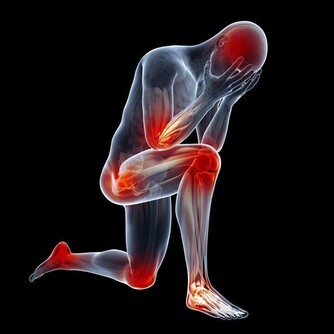

❶、【功能與主治】散瘀止血,消腫定痛。用於咯血,吐血,衄血,便血,崩漏,外傷出血,胸腹刺痛,跌撲腫痛。 ❷、【食用功效】有益氣養血、治療崩漏、產後虛弱、自汗、盜汗、有滋陽強壯作用。也治療老年人的頭風痛、腰肌痠軟無力等症。 廣告 - 請繼續往下閱讀 3枸杞